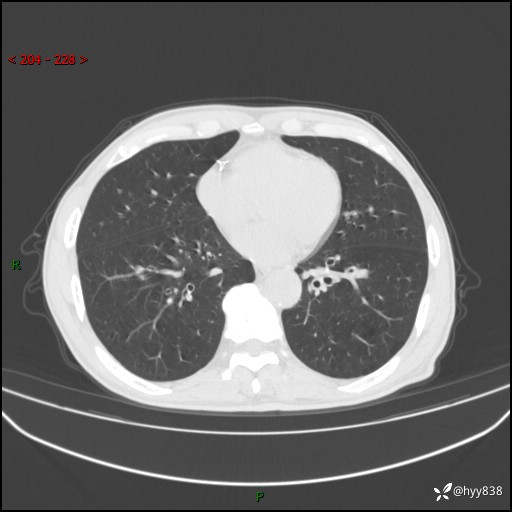

辅助检查:CT

胸部CT平扫

各期CT值:38Hu 52hu 55hu